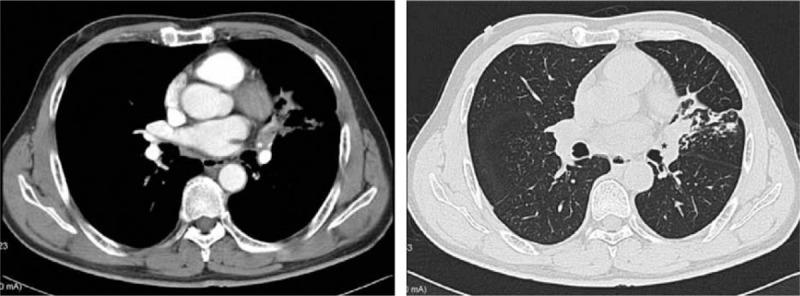

Video-assisted thoracoscopic sleeve lobectomy is safe and feasible for lung cancer. We describe a case of video-assisted thoracoscopic sleeve lobectomy via a novel single intercostal space (SIC) three-port approach.

This case demonstrates that a SIC three-port thoracoscopic approach is effective in sleeve lobectomy, and possesses potential advantages in perioperative pain management and rehabilitation.